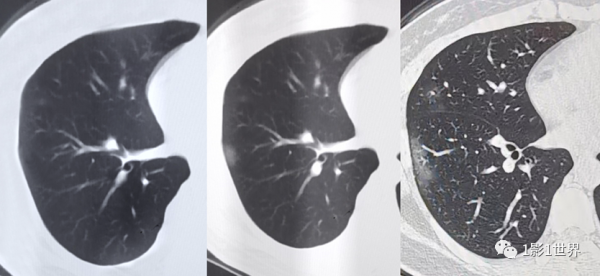

第二,未見異常,是目前沒有發現什麼問題,是疾病發展的一個階段。比如,腦外傷的病人,頭部CT未見異常,但過了幾個小時,病人煩躁不安,意識模糊了,這時立即再複查CT,發現顱內有了出血。這是一個過程,受傷當時可能真沒有出血,或出血量太少,根本看不見,但隨著時間程序,出血不斷增加,臨床症狀也開始加重,此時頭部CT也可以明確顯示病變了。再比如,現在還在肆虐的“新冠”肺炎,有些病人在胸部CT上查沒發現問題,但隨著病情進展,可能就表現出來了。

2019年武漢打工回鄉人員,發熱就診,第一天胸部CT未見異常,第2繼續複查發現肺內小片狀病變,到第3天發展很快,後核酸檢測陽性而確診。